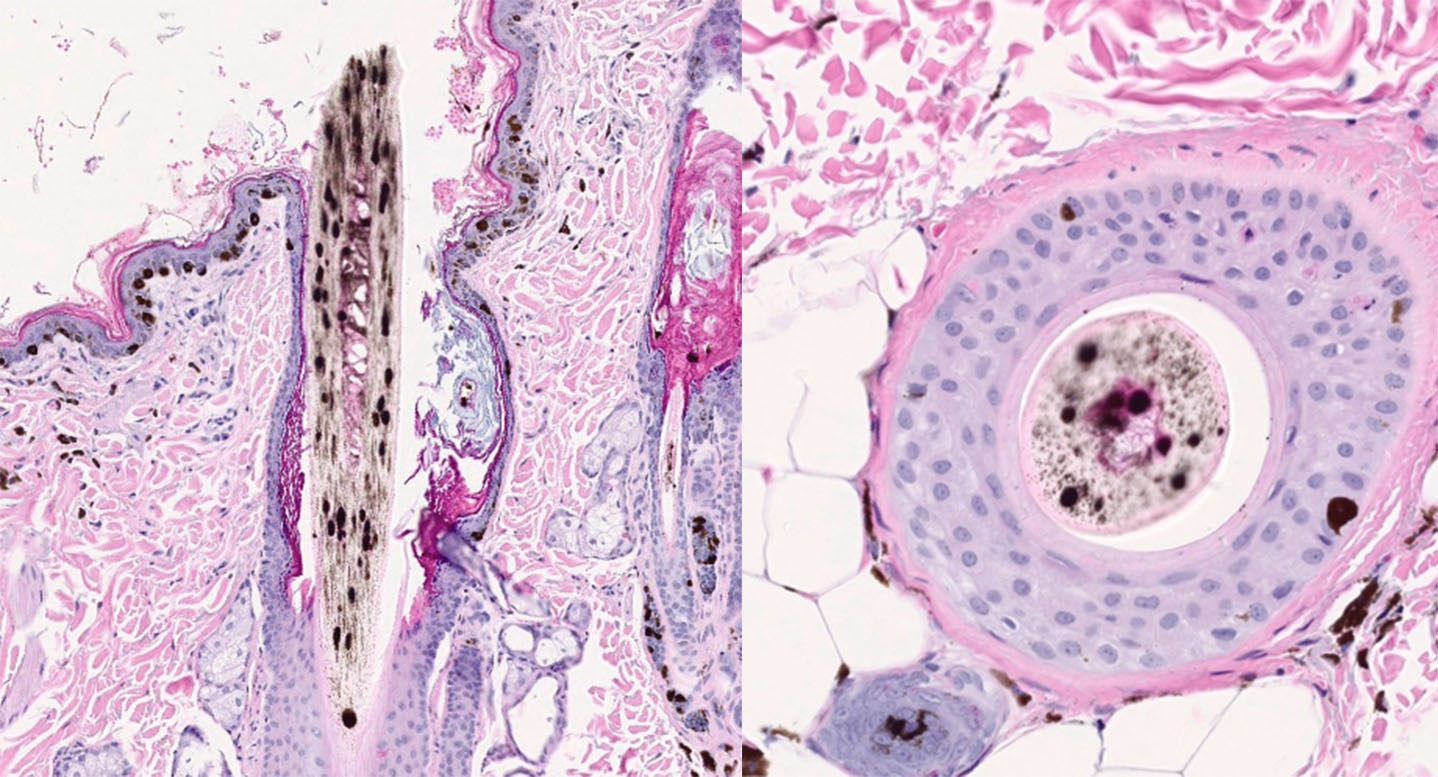

Figure 1. |

An 11-year-old, spayed female, Dachshund with a blue hair coat color presented with widespread, patchy alopecia. The patient began developing partial alopecia ten years prior on the dorsum. Three years later, the alopecia affected the trunk, and the dorsal back was almost bald. There was no pruritus, pustules, or erythema. After an additional three years, the patient developed seborrhea sicca and erythema. Cytopoint therapy was initiated at that time. The alopecia slowly progressed to the entire body. CBC/chemistry were normal. On presentation, there was partial alopecia with mild, flaky skin and hyperpigmentation, especially on the dorsal skin, as well as numerous small (1-2 mm), raised, black comedones.

Figure 2. |

Figure 3. |